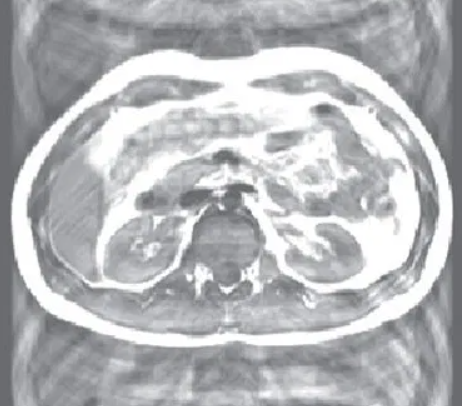

This artifact appears in the form of a ghost, made by respiratory motion in chest wall, abdominal wall and made by heart motion, blood vessels with pulse, swallowing action, and eye movement during data acquisition.

이 인공물은 ghost의 형태로 나타나는데 자료 수집 중에 움직이는 호흡 중의 흉벽, 복벽, 심장 또는 맥박이 있는 혈관, 연하작용, 안구 운동등에 의해 나타난다.